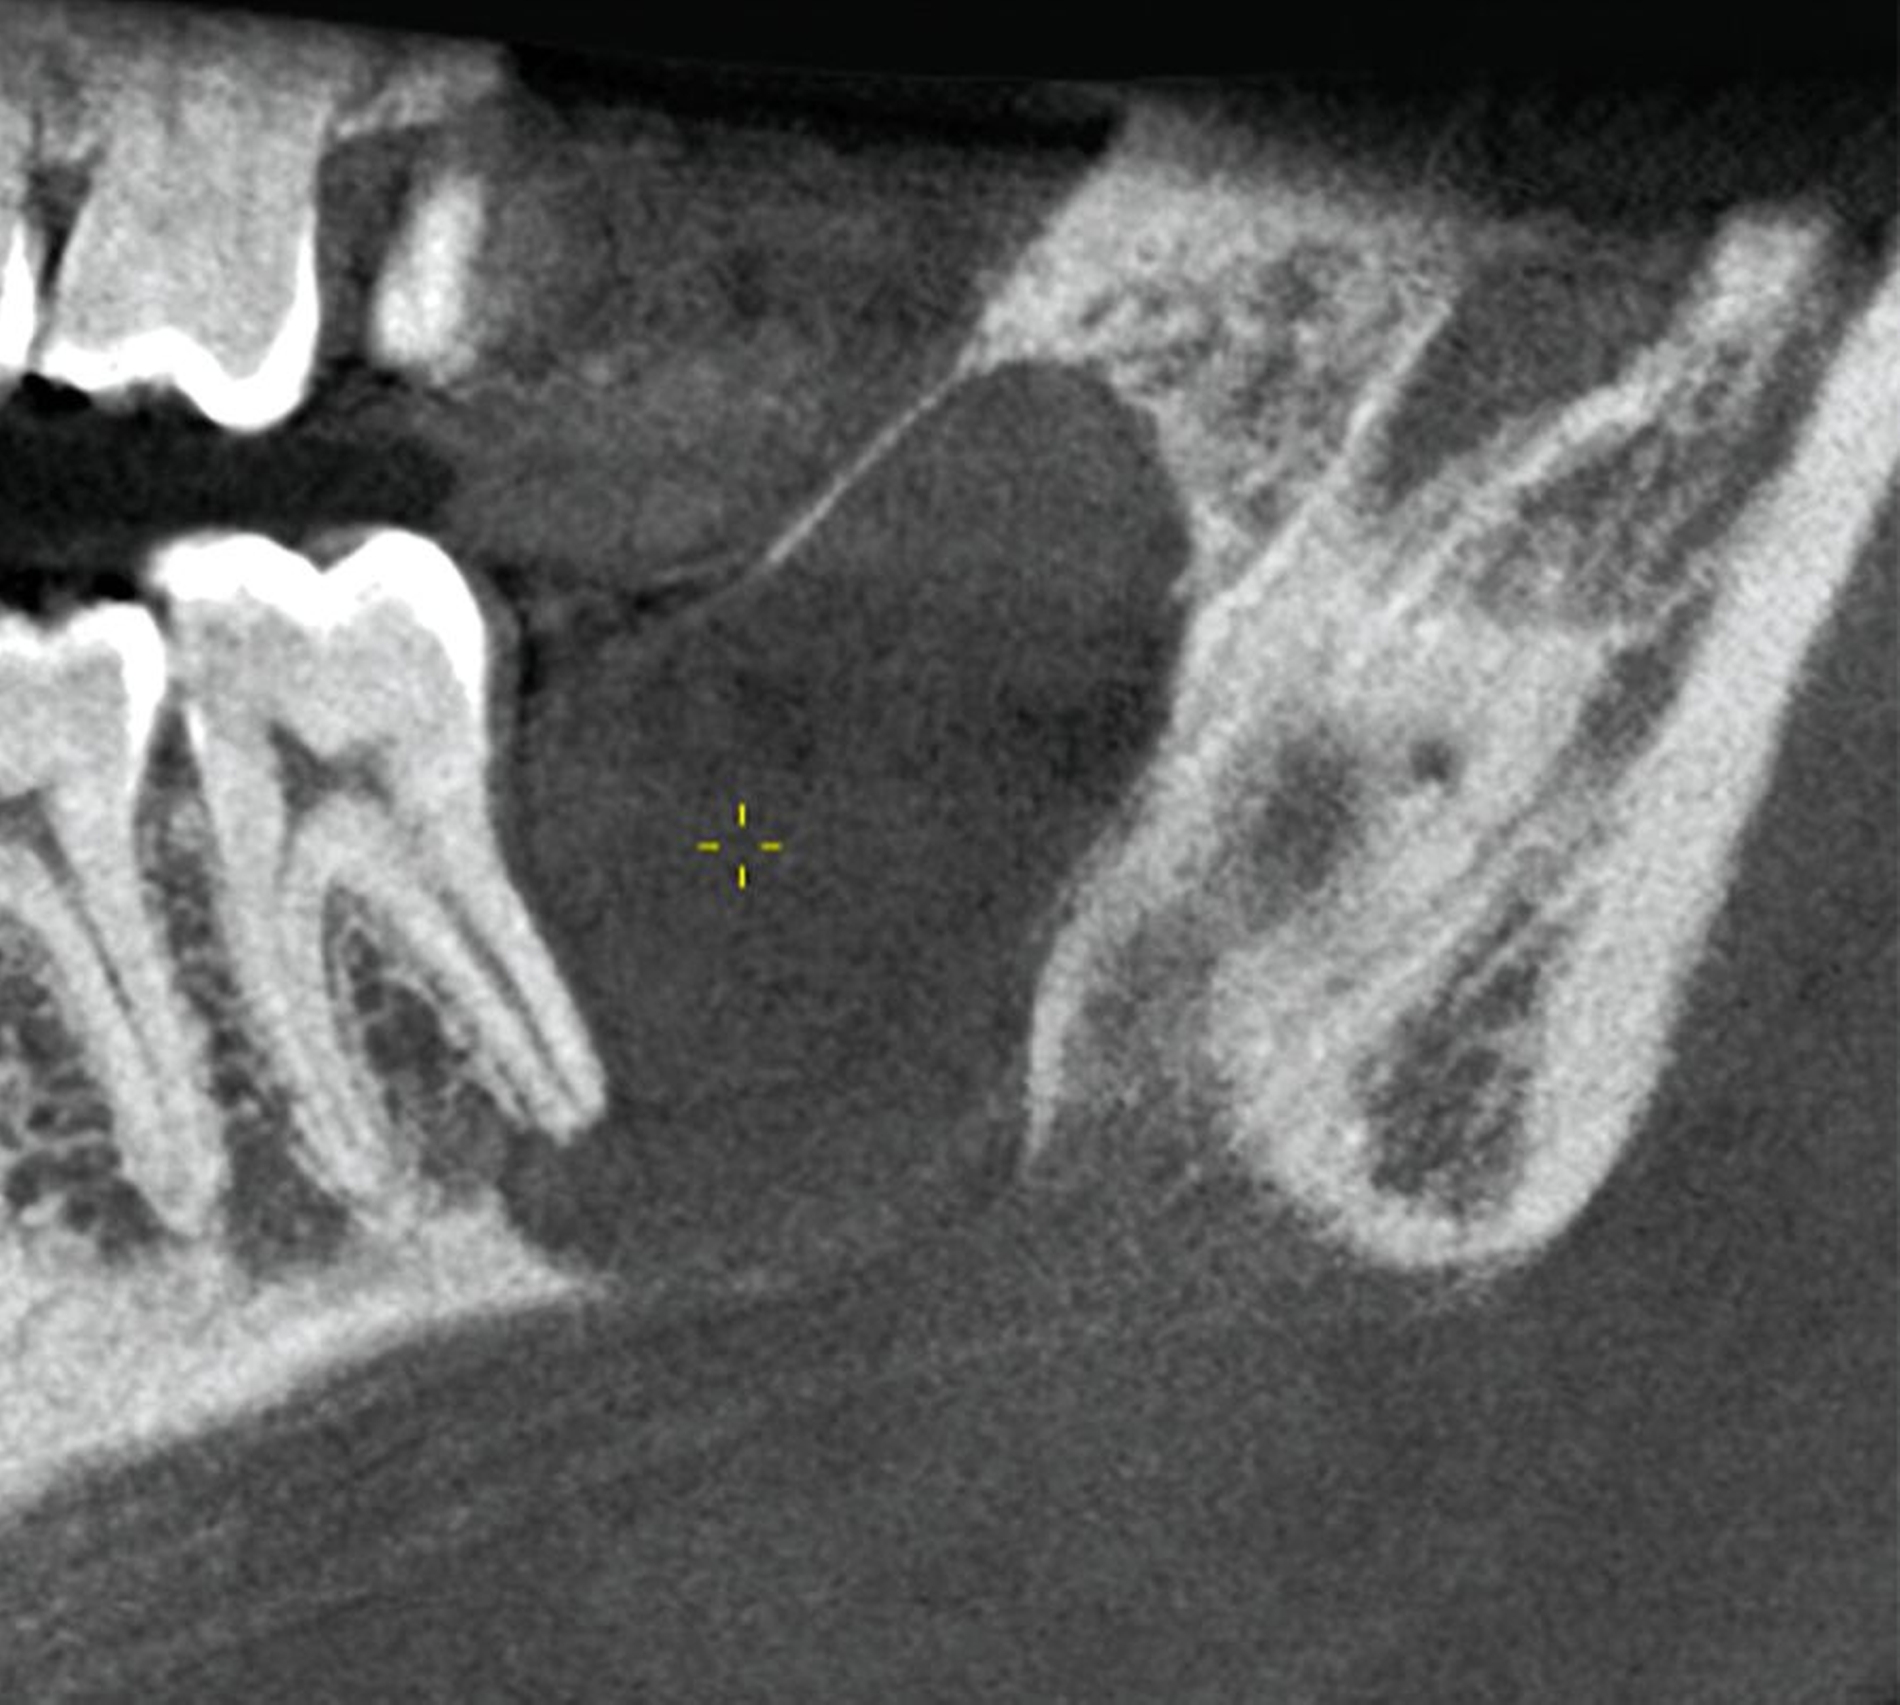

Die digitale Volumentomografie (DVT) ergab eine mehrkammerige, radioluzente Raumforderung, die sich bei erhaltener Kortikalis von der mesialen Wurzel des Zahnes 37 bis in den aufsteigenden Ast des Ramus mandibulae erstreckte (Abbildungen 1 und 2). Aufgrund der Morphologie bestand der Verdacht auf einen keratozystischen odontogenen Tumor, differenzialdiagnostisch auf andere odontogene Tumoren. Nach Aufklärung wurden die Extraktion des nicht erhaltungswürdigen Zahnes 37 sowie die Zystektomie geplant und zwei Wochen später in Intubationsnarkose durchgeführt.